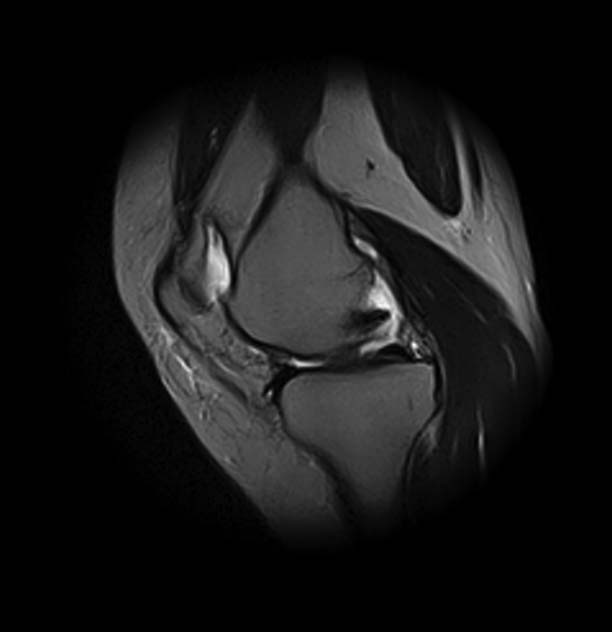

[Ortho] Показания для артроскопии

1. травма 5 лет назад - "ударилась коленом", с тех пор боли в суставе

3. стандартные рентгенограммы с небольшими изменениями - сужение

медиальной суставной щели

4. вес пациентки 80 кг, рост 165

5. сустав клинически стабилен